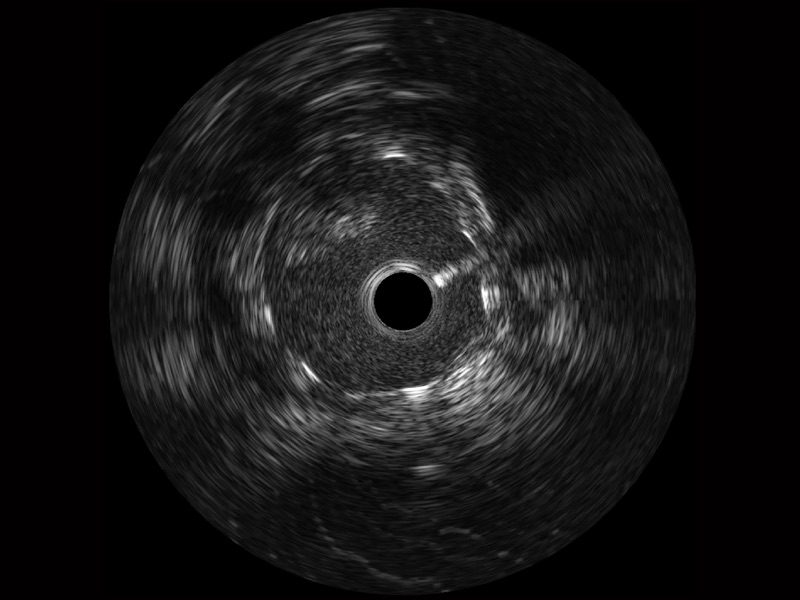

• 诸侯快讯官网宽频IVUS图像

对比传统IVUS导管成像,诸侯快讯官网宽频IVUS图像的近场支架梁显影更细腻,远场中膜外血管仍清晰可辨,兼顾远中近,兼顾分辨力与穿透深度